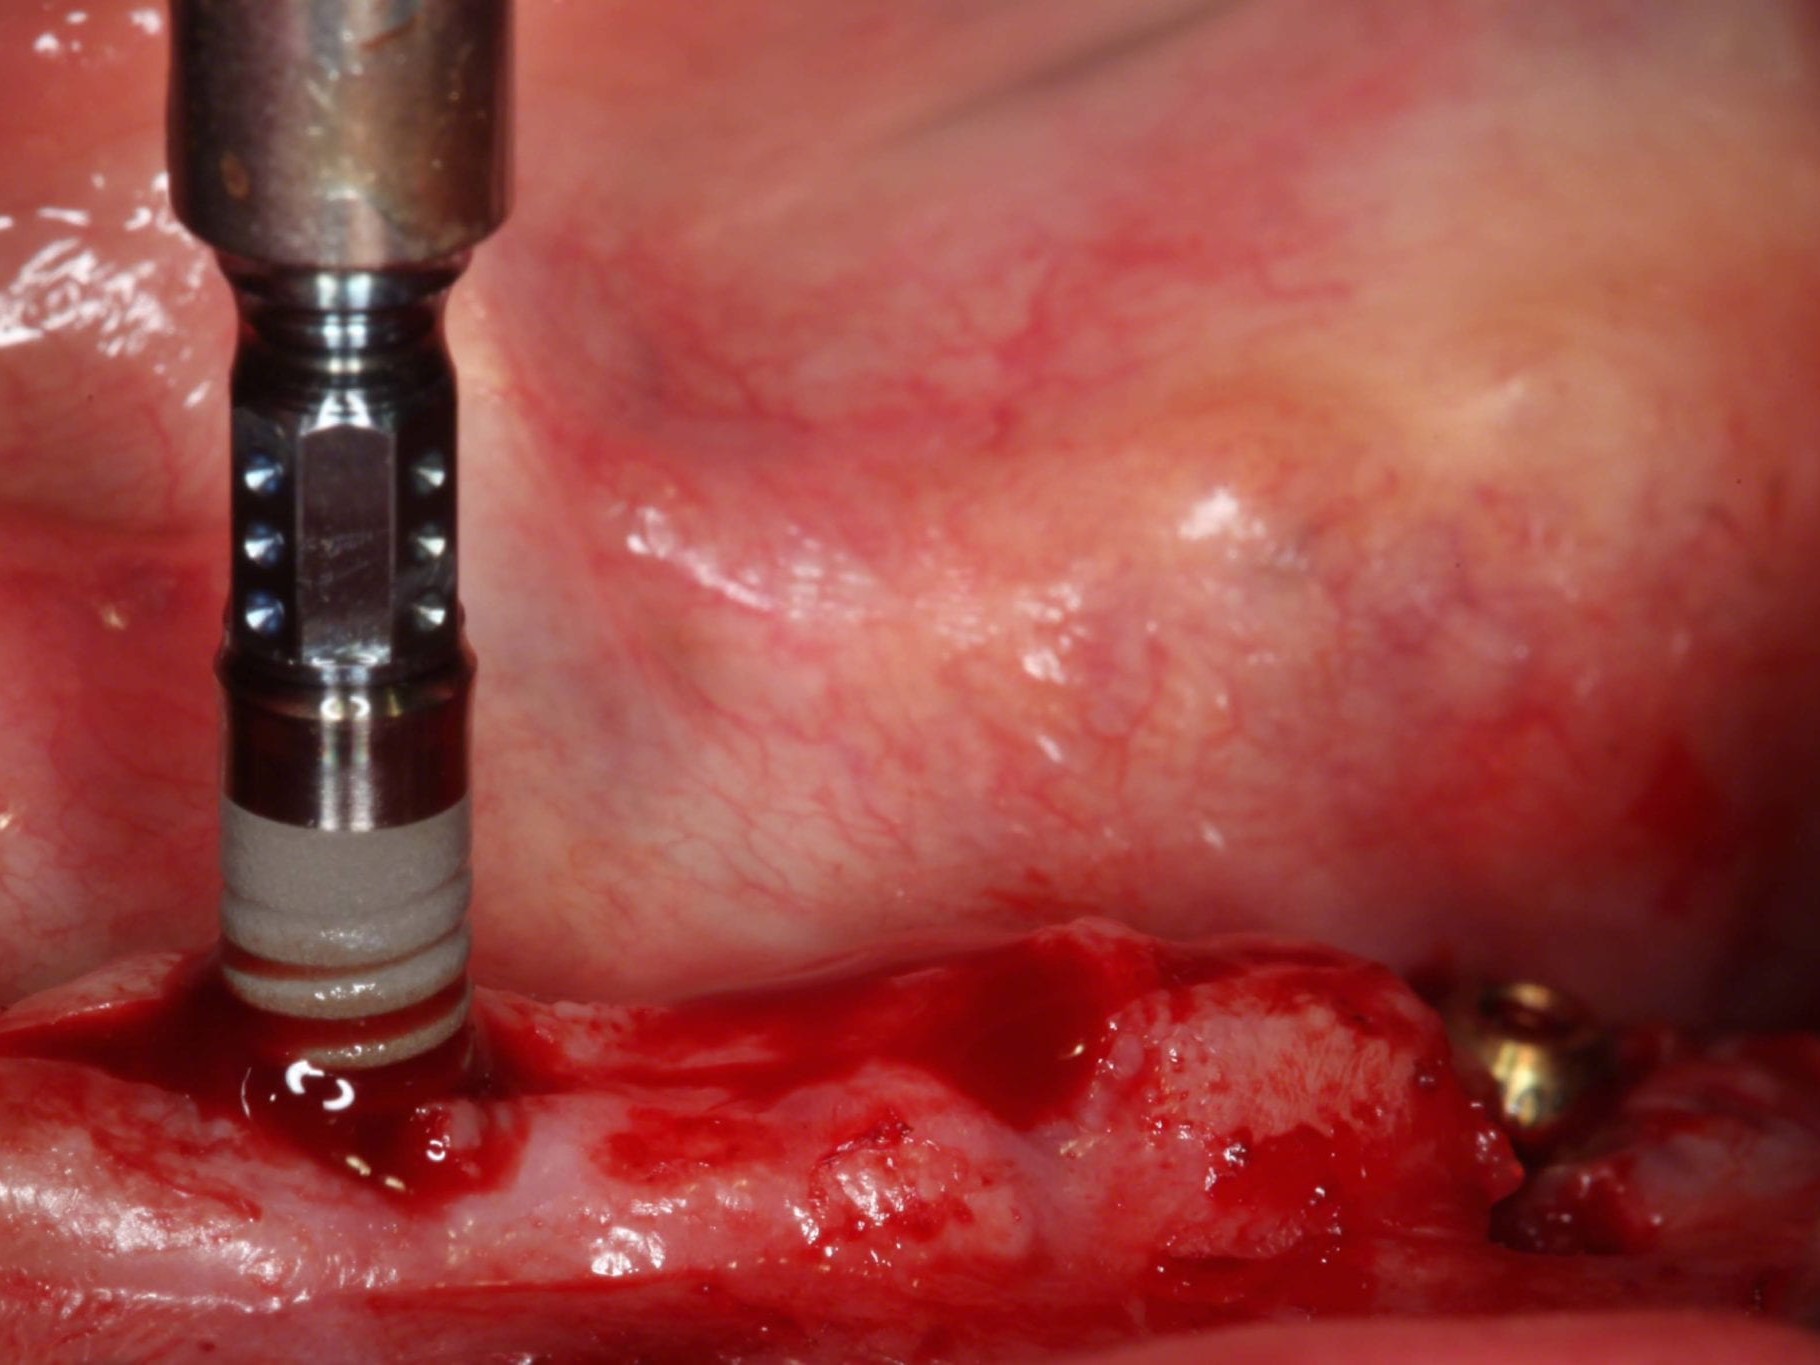

In Lokalanästhesie unter anästhesiologischem Standby mit intravenöser Antibiose mittels Clindamycin 600 mg 2mal/d wurde die Bohrschablone eingesetzt und mit Osteosyntheseschrauben fixiert (Abb. 8). Der Eingriff erfolgte nahezu flapless und somit transgingival. Nun erfolgte die Umsetzung des Straumann Hülse-in-Hülse-Konzeptes. Der Zylinder des Bohrlöffels wird in die an der Bohrschablone fixierten Hülse (Ø 5 mm) in den geplanten Regionen eingeführt. Für jeden Bohrerdurchmesser (Ø 2,2 mm und Ø 2,8 mm) ist ein entsprechender Bohrlöffel erhältlich. Jeder Bohrlöffel besitzt an seinen Enden Zylinder unterschiedlicher Höhe, die entsprechend chirurgischem Protokoll angewendet werden. Es wurden sämtliche Bohrstollen protokollgemäß aufbereitet (Abb. 9-11). Nach der Aufbereitung der Bohrstollen für die angulierten Implantate (Abb. 12-14) wurden die Straumann Bone Level Tapered Implantate (ø 3,3 mm) in regio 035 (Länge 10 mm) und 045 (Länge 12) gesetzt (Abb. 15). Abschließend wurden sämtliche Endpositionen der Implantate in regio 035 und 045 anhand der Lasermarkierungen am Übertragungsteil betreffend ihrer orovestibulären Ausrichtung exakt überprüft (Abb. 16). Nach Entfernung der Einbringhilfen und der Osteosyntheseschrauben konnte die Bohrschablone wieder entnommen werden. In regio 032 und 042 wurden nun die durchmesserreduzierten Straumann NNC (ø 3,3 mm Länge 12 mm) Implantate inseriert (Abb. 17, 18). Bei diesen Implantaten bedurfte es keiner Ausrichtung bezogen auf die orofasziale Ausrichtung. Hier musste die Insertionstiefe bezogen auf das NNC-Implantat beachtet werden (Abb. 19). Die NNC-Implantate wurden mit den entsprechenden Klebebasen versehen (Abb. 20). Danach wurden in regio 035 und 045 auf die Pro Arch Sekundärteile die dazugehörigen Retentionskappen (Abb. 21), die zur Vergrößerung der Oberfläche mit 120 μ Aluminiumoxyd abgestrahlt wurden, eingesetzt. Es erfolgte der typische Naht-Wund-Verschluss mit Einzelknopfnähten. Zum Abschluss erfolgte das prothetische Procedere mit der Eingliederung des Interimszahnersatzes in Okklusion (Abb. 22). Hierfür wurden die Retentionskappen und die Klebebasen mit dem Sofortprovisorium über ein selbsthärtendes fluoreszierendes kaltpolymerisierendes Paste-Paste-Kartuschensystem fixiert, dieser Zahnersatz extraoral versäubert (Abb. 23) und in der Mundhöhle refixiert (Abb. 24). Die Schraubenkanäle wurden mit Kunststoff verschlossen (Abb. 25). Abschließend erfolgte die radiologische Kontrolluntersuchung (Abb. 26).